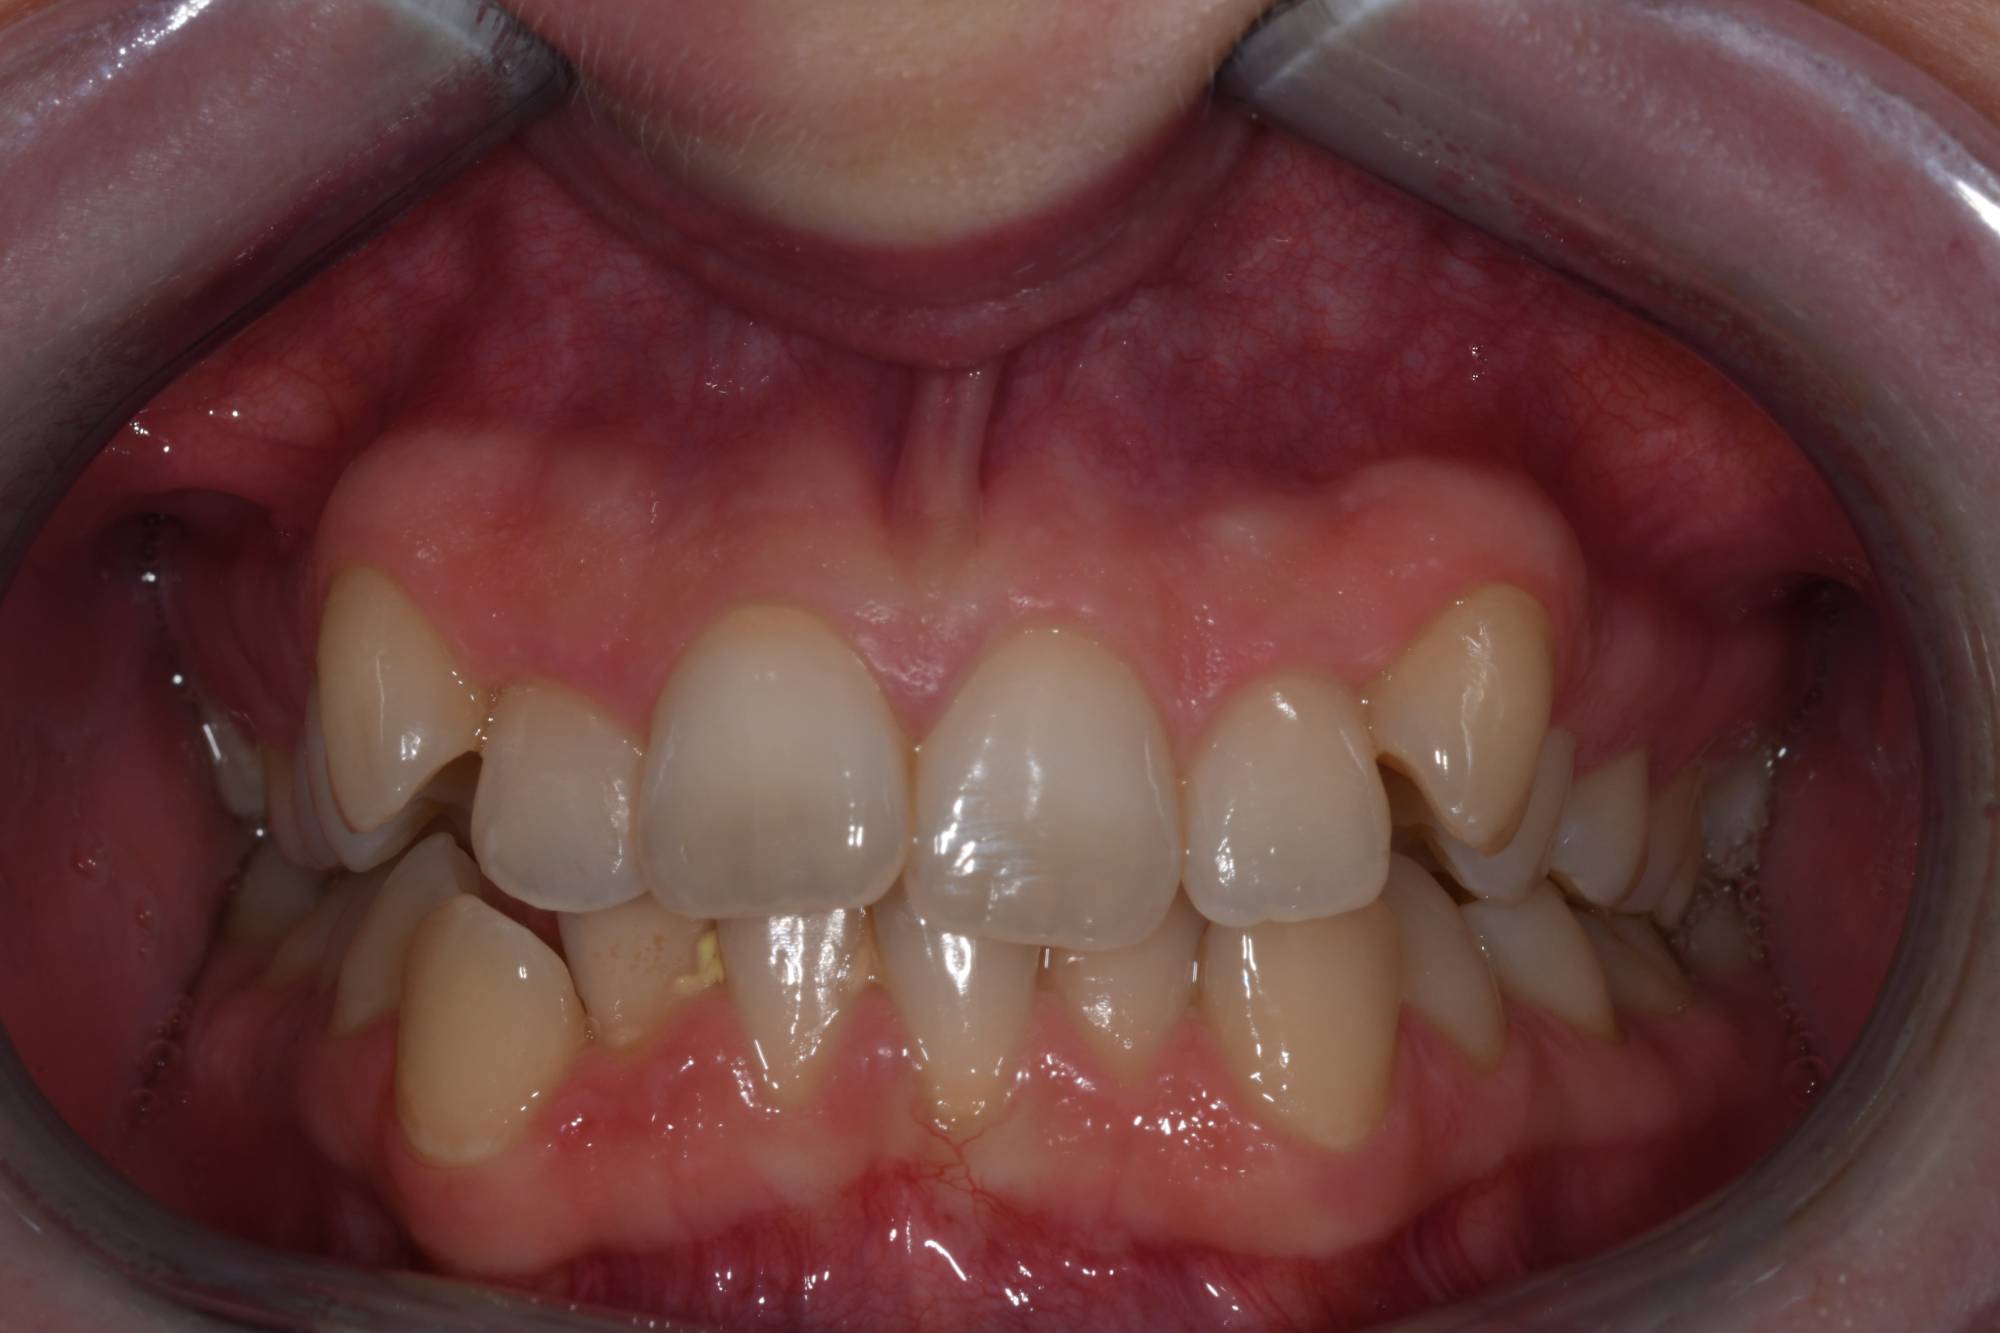

La foto dei denti che vedi appartiene ad una giovane ragazza bionda e carina. O meglio, apparteneva a quella ragazza, prima che si sottoponesse ad un trattamento ortodontico nel mio Studio a Besana Brianza per raddrizzare i suoi denti. Non solo la sua masticazione non era corretta, ma i denti anteriori erano sovrapposti e disallineati. Una condizione non complicata dal punto di vista ortodontico, ma che le rendeva la vita sociale imbarazzante. Infatti mi ha confessato che non sorrideva mai, si vergognava del suo aspetto estetico e si sentiva insicura di sé stessa. Nel suo album fotografico dei ricordi, non aveva nemmeno una foto in cui sorrideva. Hai una vaga idea dell’impatto psicologico del suo disagio? Viveva ogni situazione con timidezza.